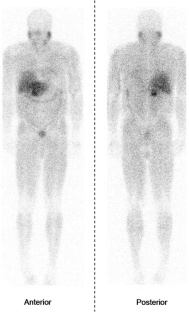

FIG. 1.

Radiolabeled metaiodobenzylguanidine scintigraphy (MIBG) can be used to image pheochromocytomas. While cross-sectional imaging techniques such as computed tomography (CT) or magnetic resonance imaging (MRI) usually localize the tumor, MIBG is often obtained to rule out multifocal and metastatic disease, and to corroborate anatomic imaging with functional data. We questioned the utility of MIBG in the diagnosis and management of pheochromocytoma.